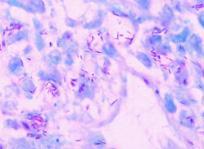

細菌(bacteria):

細菌為體積微小而結(jié)構(gòu)簡單的單細胞(unicellular)微生物。在形狀方面, 其通常可以分為

桿狀菌(bacillus)、球狀菌(coccus)、螺旋菌(spiral)及弧菌(vibrio)等。有些細菌有上述以外的外

形(例如星狀、四方形等)不過較不常見。

一般的細菌有細胞壁,其主要的成份為勝聚糖

(peptidoglycan),為其他生物所無而細菌獨具的物質(zhì)。能游泳的細菌大都具鞭毛(flagella)。在

生殖方面,其大都為無性生殖,以二分裂法(binary fission)最為普遍。在此種生殖方法中,

一個菌體分而為二, 而兩個菌體則再分而為四,如此一再地倍增。細菌是一種生存能力極強的

生物,其在地球上至少有30 億年之久。在這長久的歲月裡,其發(fā)展出攝取地球上各種各類

的營養(yǎng), 以及適應(yīng)不同環(huán)境條件的能力。其中的一些能夠行光合作用稱為光營菌(phototroph),

而另外的一些則能僅以無機物為碳素來源者稱為自營菌(autotroph)。此外尚有數(shù)目龐大能利用

有機物的細菌稱為異營菌(heterotroph)。在它們之中有些好氣(aerobic), 有些嫌氣(anaerobic),

有的則能夠在惡劣的環(huán)境(例如高溫、高壓、乾旱、奇寒等)中存活。約有80 種能引起植物

病害

顯微鏡下的細菌